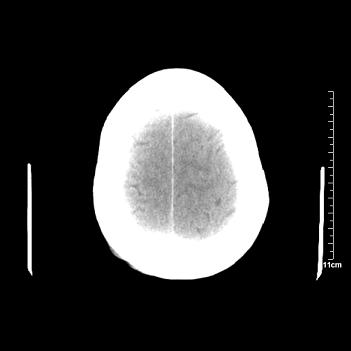

男性患者,72岁,近两天头晕来我院就诊。 因患者血压太高而未做增强,建议病人去市医院做mri检查。等得到mri随访结果再公布给大家。 测及左颞顶枕叶病灶ct值分别为5hu 30hu 729hu。

考虑左侧颞顶枕叶少突胶质细胞瘤。 今天随访患者手术病理结果 病理回报为胶质瘤2级 钙化

左侧颞顶枕叶大片状低密度影,呈均一水样密度,边界清楚,病灶边缘不规则片状钙化,左侧脑室后角扩大,中线结构未见移位,综合来看不像肿瘤,软化灶,钙化不好解释

左侧颞顶枕叶巨大囊性病灶,灶内见小片实性区且灶内及灶周围大量团块状钙化影,灶周水肿少.左侧室枕角内见环形钙化,可见较清晰前壁,钙化与室壁似有间隙.

囊变明显,钙化明显,部分实性组织,轻度占位,左侧脑室受压---考虑 少突胶质细胞瘤,畸胎瘤,寄生虫病

今天追踪患者家属手术病理结果 病理回报为胶质瘤2级并钙化

病理回报为胶质瘤2级并钙化